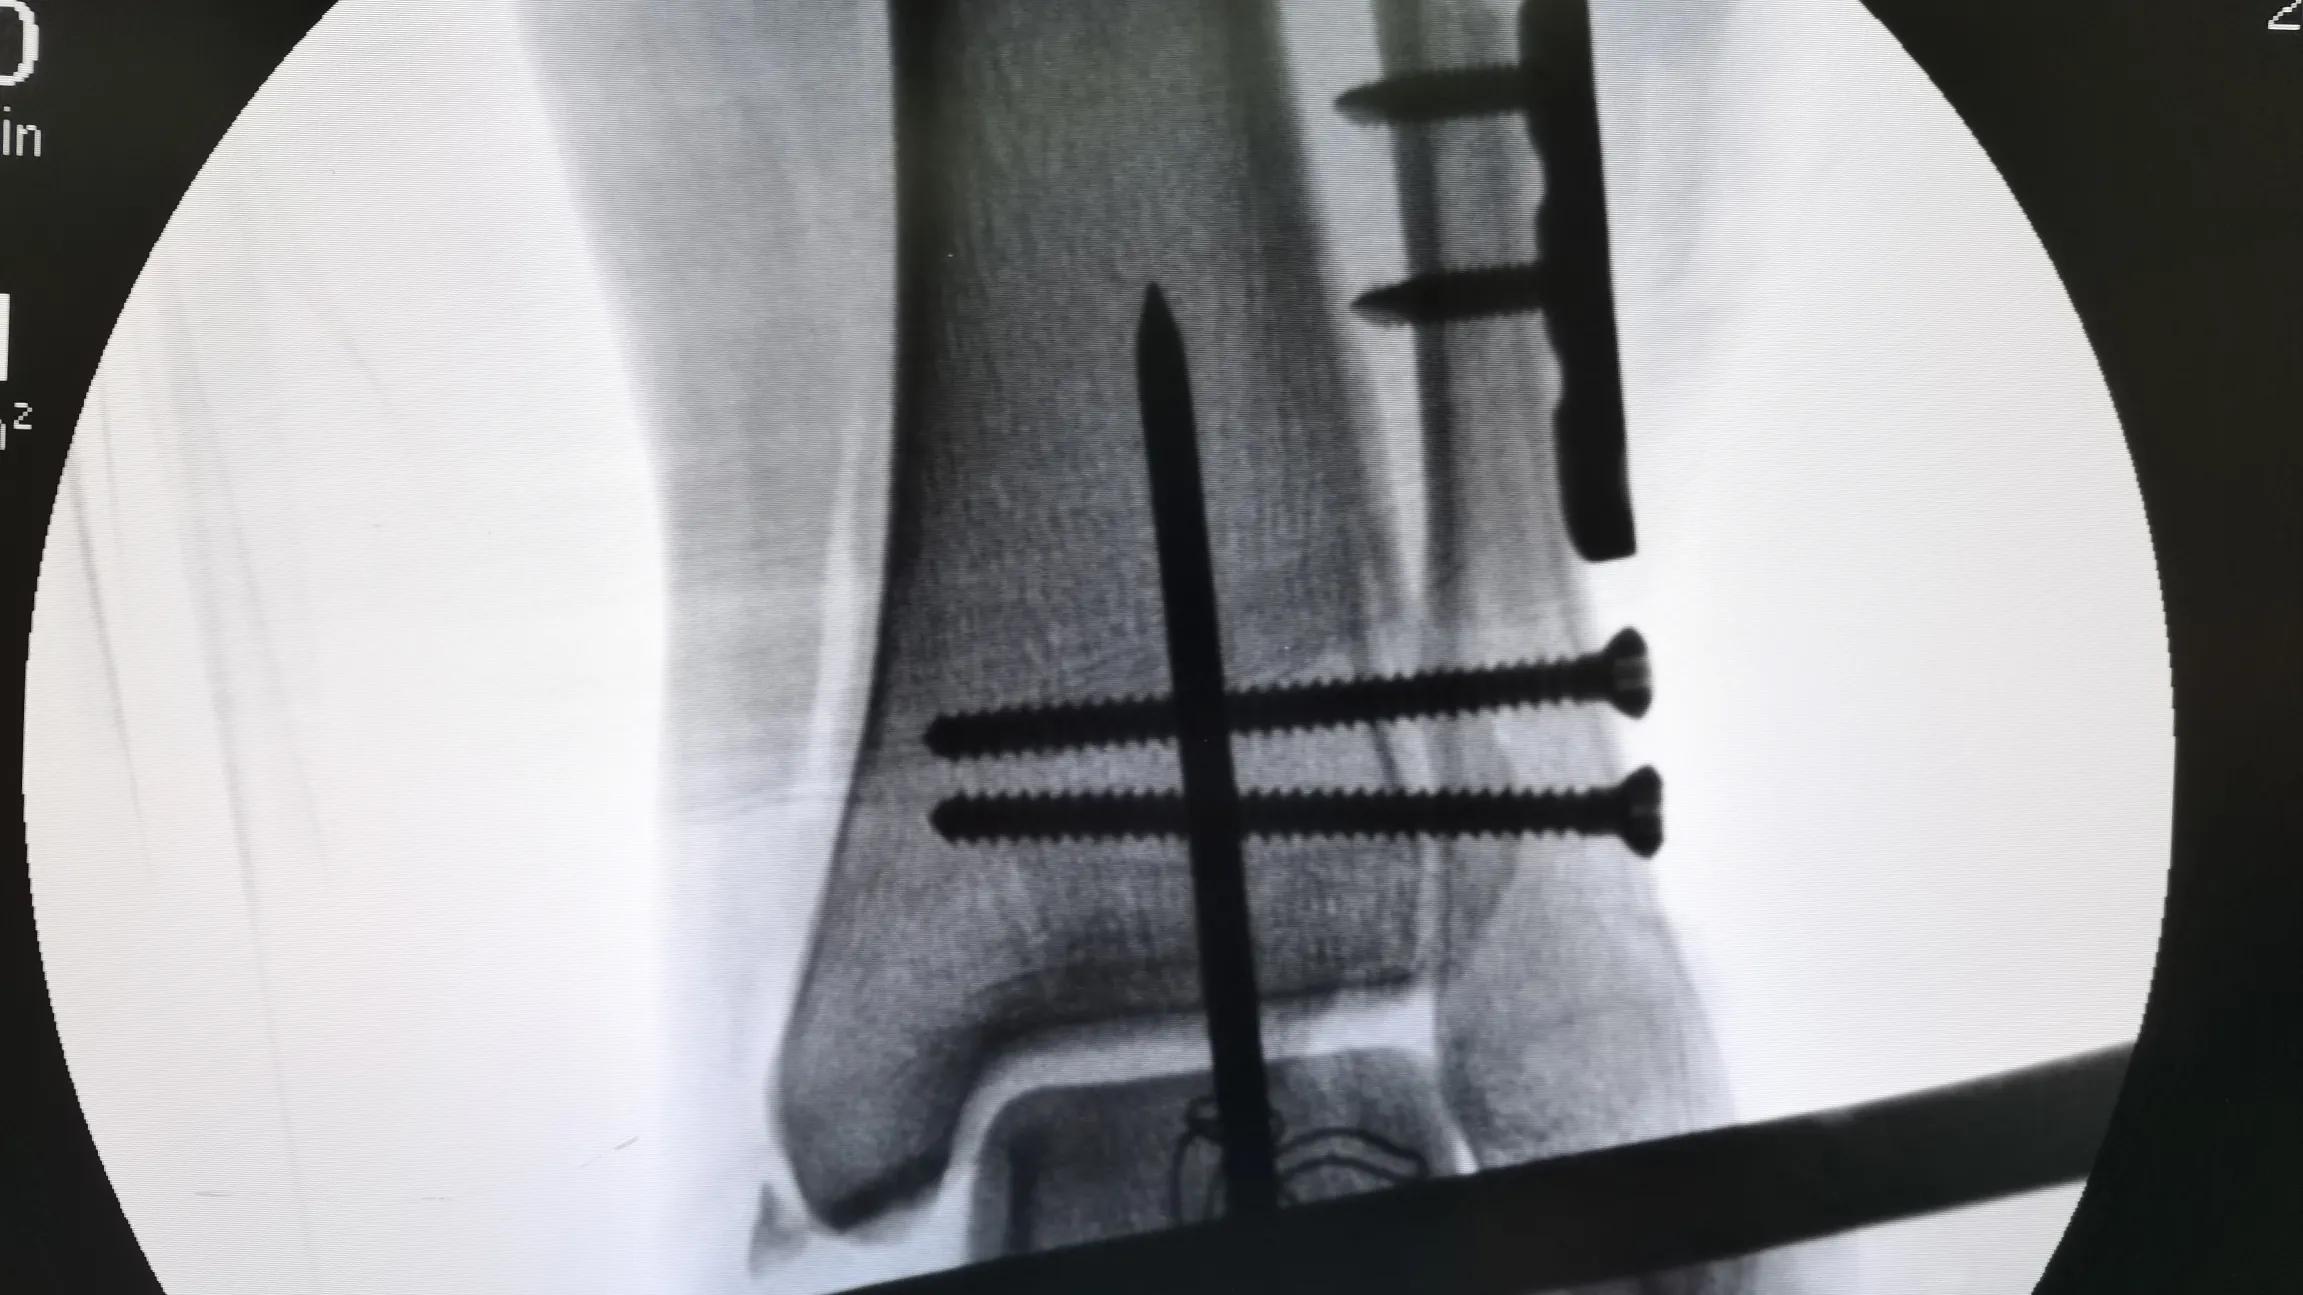

对于内固定物是否要取出来,分以下几种情况:

必须取出来的情况

- 异物反应 :有一少部分人出现内植入物排斥反应,表现为局部红肿、破溃、切口愈合困哪,需要取出。

- 内固定物失败 :内固定物断裂、严重感染时通常 需将内固定物取出。

- 手术涉及活动的关节 :如下胫腓拉力螺钉,植入目的是保证下胫腓韧带牢固愈合,由于下胫腓是一个微动关节,下地活动前需将拉力螺钉取出,以免出现螺钉断裂,难以取出。

以下情况建议取出来

- 年轻人、身体条件好的病人,正在发育的儿童、青少年患者 。

- 不锈钢的内固定物 :通常植入不锈钢材质的钢板螺钉的患者无法行核磁检查,因某些疾病(如脑血管病、脊髓疾病等)需要行核磁共振检查已指导治疗,所以防患于未然,建议骨折愈合后尽量取出不锈钢材质的钢板及螺钉、钢丝等。

- 特殊部位 :如某些部分皮肤软组织薄,形象的说如“皮包骨”的地方,钢板与皮肤反复摩擦容易导致皮肤破溃、内固定物外露,如尺骨鹰嘴等部位。

以下情况不建议取

- 老年患者,年龄超过60岁, 如无明显不适,建议不取。

- 时间长 :一般超过三年,骨头和螺钉间的粘连易造成螺钉滑丝,增加取出困难及手术创伤,大大延长手术时间。

- 内固定物周围血管神经密集交错部位不建议取出 。因第一次手术时,局部解剖结构较为清晰,依照解剖结构进行仔细剥离,一般不会损伤重要血管及神经,第2次手术时因瘢痕组织大量增生,血管、神经解剖层次混乱不清,手术中非常容易损伤,所以无特殊必要,一般不建议取出。

- 断在骨头内的螺钉 ,取出时会明显增加手术创伤。

- 某些特殊设计的螺钉 : 如Herbert螺钉、骨铆钉,根本取不出来。

所以说,内固定取不取要根据具体病情而定!